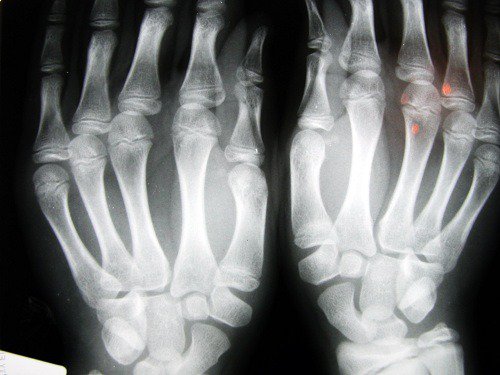

2. Nivelrikon kehittymisen todennäköisyys

Iso-Britannian Nottinghamin yliopistossa tehdyn tutkimuksen mukaan lyhyen etusormen omaavilla ihmisillä on korkeampi riski saada nivelrikon tapaisia ongelmia. Nämä ongelmat on yhdistetty siihen, että estrogeenia on vähemmän ja liikuntaa ei harrasteta tarpeeksi, ja riski tällaisten pulmien kehittymiseen on suurempi naisilla.